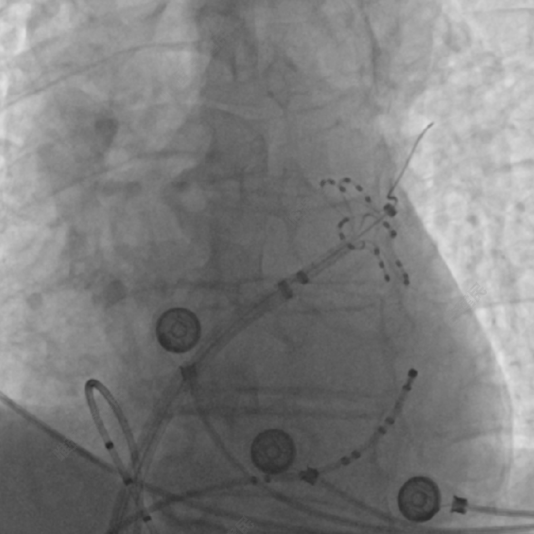

术中采用32mm规格CardioPulse™脉冲消融导管完成了4个肺静脉的电隔离,如图2为左下肺静脉与右上肺静脉消融DSA影像,肺静脉口内消融电极呈篮状,肺静脉口部及前庭部位消融电极呈花瓣状,消融后肺静脉电位消失,实现肺静脉完全隔离。

(a)左下肺静脉消融

(b)右上肺静脉消融

图2 采用CardioPulse™脉冲消融导管进行肺静脉消融